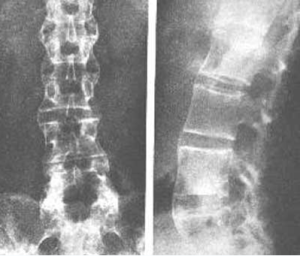

以骶髂關節炎最為突出。骶髂關節出現x線徵象時往往已較遲,幾乎完全是雙側性。最初出現的是關節附近有斑片狀骨質疏鬆區,特別是骶髂關節的中下段最為明顯。接著便出現了骨腐蝕與軟骨下骨皮質硬化。在骶髂關節的中下段,髂骨面覆蓋著薄層軟骨,因此該處首先出現骨骼變化,且比較明顯。在骶髂關節的上1/3處,有堅強的韌帶連線著骨面,也可以有類似的X線徵象。軟骨下骨侵蝕的X線表現為關節間隙的假性增寬。接下去便是纖維化、鈣化、骨橋形成與骨化。一般說來,軟骨下骨皮質硬化比骨腐蝕明顯些,最終骶髂關節完全強直,通常需數年之久。

在脊柱方面主要表現在椎間盤、脊椎小關節、肋脊關節,後縱韌帶與寰樞關節。很少有上述關節出現病變而骶髂關節卻不受侵犯。早期階段,椎間盤纖維環淺層有炎症,伴反應性骨硬化與鄰近椎體腐蝕,使椎體變成方形。纖維環逐漸骨化,並有骨橋形成。同時脊椎後關節和鄰近韌帶亦有類似的變化,最終脊柱完全融合,如竹節狀。強直性脊柱炎的患者還可以出現椎間盤周圍椎體骨質腐蝕和硬化,竹節狀改變亦在此節段中斷,通常發生在疾病的後期。臨床上常有急性發作,並有局限性疼痛。該區常有上述X線徵象,稱為"椎間盤炎"。這種病變易誤診斷為結核、化膿性骨髓炎,甚至認為是轉移性病灶。

周圍大關節炎症以髖關節最常見。表現為對稱性、均勻性關節間隙狹窄,軟骨下骨板不規則骨硬化,關節外緣骨刺形成,最後骨性強直。肩關節為第二好發部位,病變情況與髖關節相類似,骨腐蝕主要發生在肱骨頭外上方。